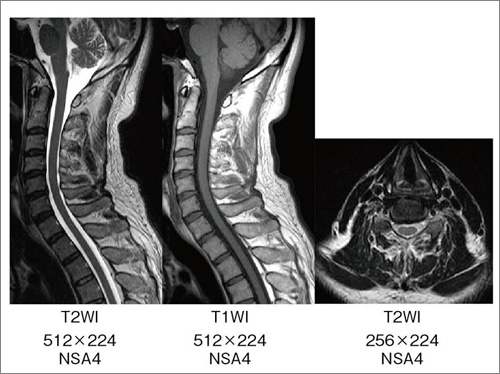

脊椎

脊椎の撮像法を表1-(5)に,画像を図7に示す。当院では脊椎は,あまり時間をかけず,どの検査も15〜20分で終わるようにしている。

図7 脊椎